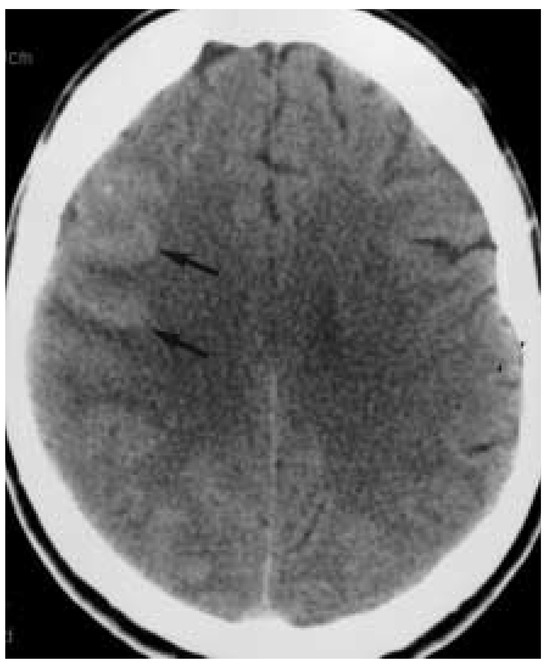

This is a case report of a 51-year-old woman who 10 days after carotid endarterectomy developed a hyperperfusion syndrome characterised by headache, systolic blood pressure values around 280 mm Hg, a possible single seizure, focal neurologic deficits, elevated intracranial blood velocities on transcranial [...] Read more.

This is a case report of a 51-year-old woman who 10 days after carotid endarterectomy developed a hyperperfusion syndrome characterised by headache, systolic blood pressure values around 280 mm Hg, a possible single seizure, focal neurologic deficits, elevated intracranial blood velocities on transcranial Doppler, and focal brain oedema on brain CT with luxury perfusion. Treatment with antihypertensive drugs led within a few days to a regression of clinical, Doppler, and radiologic changes. Full article

Show Figures

Figure 1